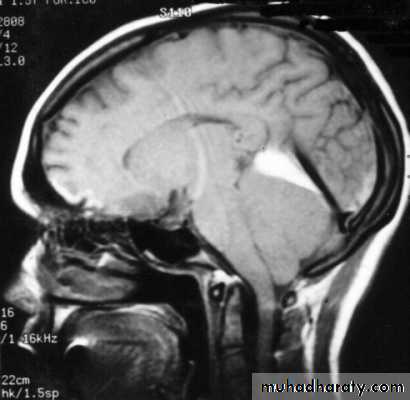

7. Cerebral Herniation

a. Subfalcine Herniation

b. Uncal Herniation

c. Tentorial Herniation

d. Tonsillar Herniation

a. Transtentorial Herniation